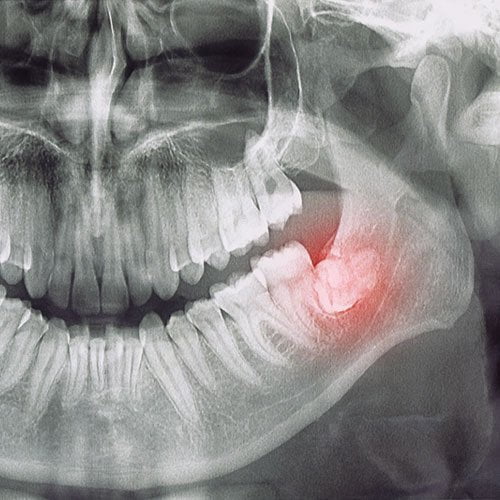

Wisdom teeth

Wisdom teeth often emerge without a warning. When your wisdom tooth breaks through the gums, it causes unbearable pain.